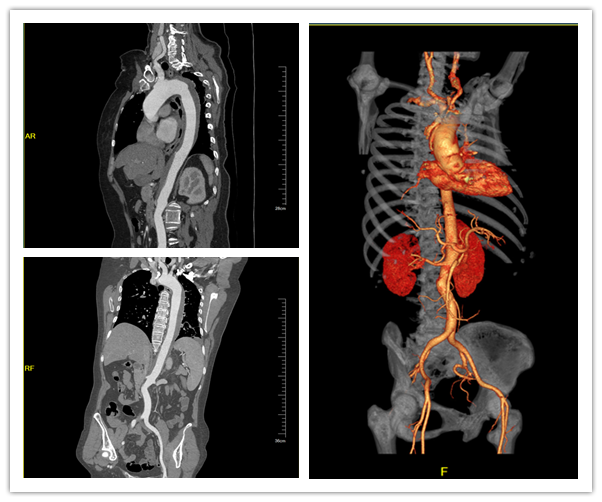

病例三

王某某,男,68岁,突发剧烈难以忍受的胸腹部切割样疼痛;经急救判断其主诉表现为胸痛三联征,按照流程进行紧急处理,经查心电图未见明显异常,遂进行主动脉CTA检查;经扫描完成后,将扫描图像载入AVA插件后,插件自动提取主动脉血管生成VR和MPR图像及分析数据,可见从主动脉弓至髂动脉大范围假腔,帮助临床快速发现并明确诊断其为Ⅰ型主动脉夹层,主动脉夹层为十分凶险的疾病,及时的发现及快速的干预对挽救患者生命至关重要。